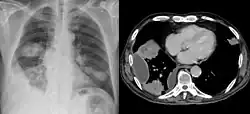

Die Aktinomykose ist eine bakterielle anaerobe und aerobe Mischinfektion, die vor allem durch Actinomyces israelii, aber auch andere Aktinomyzeten hervorgerufen wird. Dieser gehört zur normalen Mundflora des Menschen und dringt bei einer Verletzung der Schleimhaut in tiefere Gewebeschichten ein. Hier kommt es nun zu einer eitrigen Entzündung mit der Ausbildung von Granulationsgewebe und verzweigter Fisteln. Das häufigste klinische Erscheinungsbild ist die zervikofaziale Aktinomykose (also am Hals, im Gesicht – zum Beispiel als Canaliculitis lacrimalis, meist im Mundbereich), wohingegen das Auftreten im ZNS, der Lunge (durch Aspiration) sowie in der Haut selten ist. Beschrieben sind auch Aktinomykosen der Brustdrüse, sowie im Genitalbereich, meist im Zusammenhang mit lange liegenden Intrauterinpessaren.[3][4]

Die Hauptkomplikation besteht in der bei der Aktinomykose vorkommenden Fistelbildung. Dadurch können die Erreger in den Blutkreislauf gelangen und die Krankheit kann systemisch (den ganzen Körper betreffend) werden. Durch die hohe Rezidivität ist die Prognose nicht gut. Die thorakale Infektionsform (engl.: thoracic actinomycosis) bleibt unbehandelt mit einem hohen Risiko für Gesundheit und Leben der Patienten belastet. Auch ausgedehnte thorakale Erkrankungen sprechen sehr gut auf antibiotische Therapie an. Eine operative oder interventionelle Therapie (Drainage) wird zurzeit in ca. der Hälfte der Fälle durchgeführt, was wahrscheinlich zu oft ist.